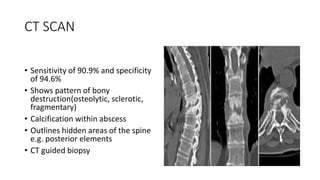

CT SCAN

• Sensitivity of 90.9% and specificity

of 94.6%

• Shows pattern of bony

destruction(osteolytic, sclerotic,

fragmentary)

• Calcification within abscess

• Outlines hidden areas of the spine

e.g. posterior elements

• CT guided biopsy